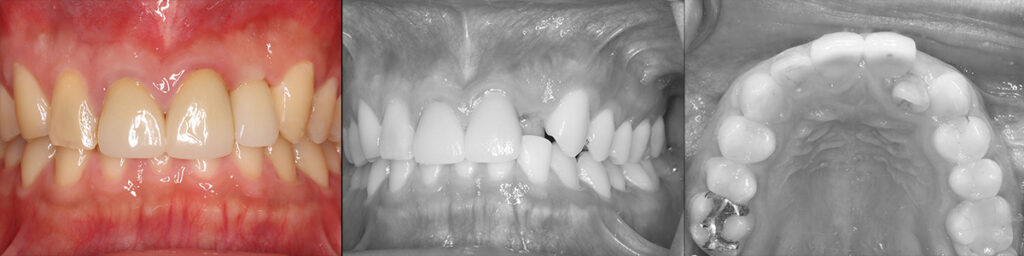

治療直後の上下前歯の被蓋関係と術前の状態